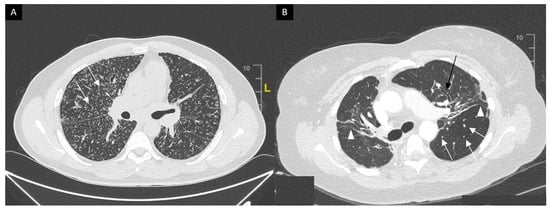

This system was developed prior to computed tomography (CT) and is widely used for its prognostic value. Mediastinal lymphadenopathy, especially right paratracheal and aorto-pulmonary locations, are commonly observed on chest CT. Calcifications [33] of lymph nodes may occur in sarcoidosis; they are usually chalky, focal and tend to be bilateral when present [33]. Chest CT is much more sensitive than CXR for the detection of lung nodules and subtle fibrosis. Pulmonary nodules tend to be tiny, usually termed “micronodules” ranging from 2 to 5 mm, typically located along the bronchovascular bundles, interlobular septa, interlobar fissures and subpleural regions, which constitute the “perilymphatic distribution (Figure 2A). Pulmonary fibrotic changes may be a dominant feature with typical features of architectural distortion, volume loss and bronchiectasis, which tend to predominate in the middle and upper lung zones (Figure 2B). Recently, the “dark lymph node” or the “cluster of black pearls” sign (defined by tiny round nodules each measuring 1–2 mm which are seen uniformly distributed throughout all or part of the lymph node) has been described as relatively specific of sarcoidosis with negative and positive predictive values of 96 and 91%, respectively [34]. The “galaxy” sign is also highly suggestive for sarcoidosis; it consists of a large nodule, usually with irregular boundaries, surrounded by a border of tiny satellite nodules. Alveolar, pseudo-alveolar consolidations, or diffuse ground glass are rarely the cause of sarcoidosis-associated radiological abnormalities [35].

Figure 2. (A) Perilymphatic micronodules predominant in the right lung (white arrows). (B) Reticular opacities (white arrowheads), extensive traction bronchiectasis (black arrows) and perilymphatic nodules (white arrow) on lung windows. Findings consistent with sarcoidosis along with fibrosis.